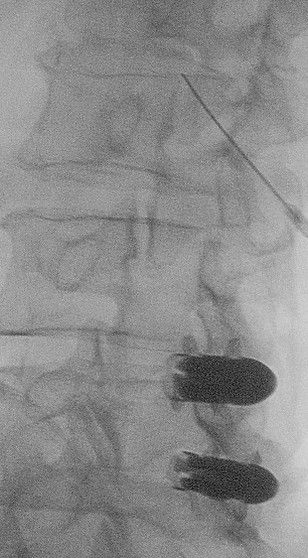

Blocco delle faccette L4-L5 sinistro : L'immagine a sinistra mostra chiaramente la fessura articolare L4-L5 grazie a una proiezione obliqua di circa 30 gradi. L'immagine centrale mostra l'ago nella parte cranica dell'articolazione della fessura L4-L5. L'immagine a destra mostra l'artrografia L4-L5 con una fine fessura.

Blocco di faccette L3-L4 destro : L'immagine a sinistra mostra chiaramente la fessura dell'articolazione L3-L4 grazie a una proiezione obliqua a circa 30 gradi. L'immagine centrale mostra l'ago nella parte cranica dell'articolazione della schisi L3-L4. L'immagine a destra mostra l'artrografia L3-L4 con una fessura molto fine .